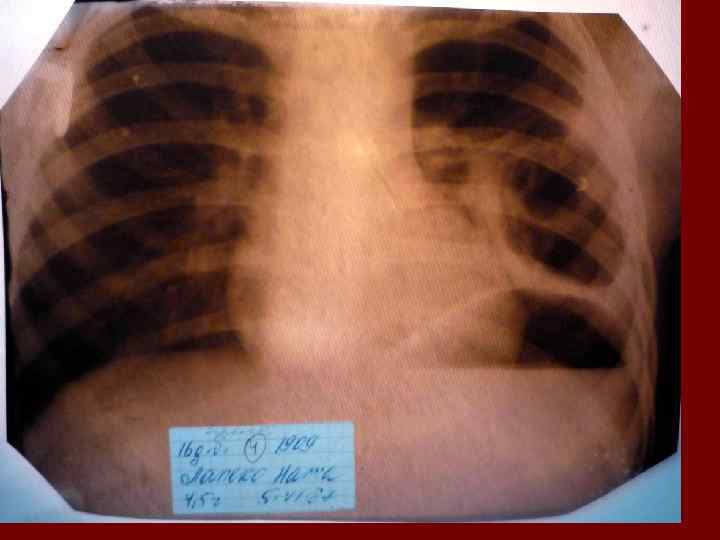

Пневмония Воспалительный процесс в респираторных отделах легкого с наличием внутриальвеолярной экссудации. n Это острое инфекционное заболевание легочной паренхимы, диагностируемое по синдрому дыхательных расстройств и/или физикальным данным при наличии очаговых или инфильтративных изменений на рентгенограмме. n Пневмония – это, прежде всего, клинический диагноз, который ставит врач у постели больного, и только затем подтверждает рентгенологически. n

Пневмония - это неспецифическое воспаление легочной ткани, в основе которого лежат инфекционный токсикоз, дыхательная недостаточность, водно – электролитные и прочие метаболические нарушение с патологическими изменениями во всех органах и системах детского организма. Заболевание диагностируется на основании синдрома дыхательных расстройств и/или физикальных данных и верифицируется рентгенологически выявлением инфильтративных изменений в легких.

Долевая пневмония характеризуется лобарным пневмоническим инфильтратом. Крупозная ( пневмококковая) пневмония диагностируется прежде всего по клиническим данным. Крупозная пневмония сохраняет свою типичную картину пневмококковой пневмонии: острое начало с характерными клиническими данными, циклическое течение, несклонность к деструкции, гомогенной и лобарной инфильтративной тенью при рентгенологическом исследовании. Вместе с тем, широкое использование антибиотиков способствовало значительному снижению числа крупозных пневмоний у детей. Интерстициальная – редкая форма пневмоний, при которой оказывается поражен прежде всего интерстиций. Как правило, интерстициальная пневмония обусловлена вирусами, пневмоцистами, внутриклеточными микроорганизмами и грибами.

Морфологическую форму пневмонии определяют по клинико – рентгенологическим данным: выделяют очаговую, очагово – сливную, долевую ( крупозную), сегментарную и интерстициальную пневмонии. Очаговая – наиболее распространенная форма. Пневмонические очаги чаще бывают размером 1 см и более. Очагово – сливная – инфильтративные изменения в нескольких сегментах или во всей доле легкого, на фоне которых могут быть видны более плотные участки инфильтрации и/или полости деструкции. Сегментарная – в процесс вовлекается весь сегмент, который, как правило, находится в состоянии гиповентиляции, ателектаза. Морфологическая картина воспаления при очаговых и сегментарных пневмониях связана с первичным инфекционным воспалением в бронхах, что дает основание отнести эти варианты поражения легочной ткани к бронхопневмониям, нередко сопровождающихся бронхообструктивным или бронхообтурационным синдромами. В настоящее время данный тип пневмоний у детей встречается наиболее часто.